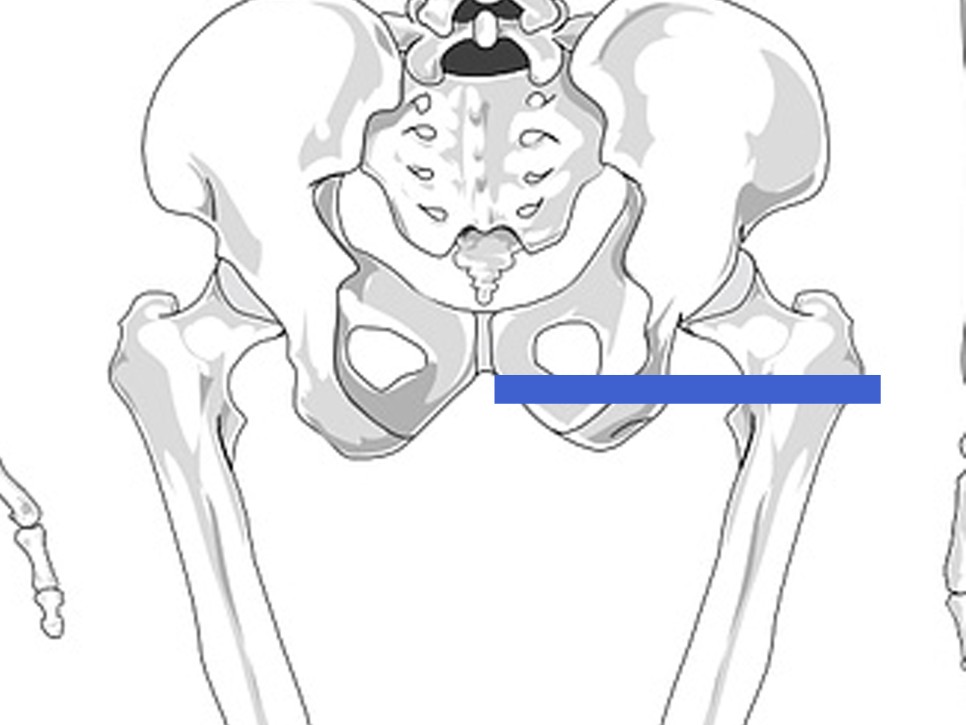

- 한쪽 다리는 뻗고 반대쪽 다리의 무릎은 굽혀서 한쪽 다리 위로 교차합니다- 양팔은 뒤로 해서 받쳐줍니다.- 골반 아래에 막대기, 절구를 위치시킵니다. 위치는 대체로 상단 골사진의 파란색 부분입니다.- 10초 정도 살짝 눌러줍니다. 미세하게 움직이며, 시간과 강도를 자신에게 맞게 조절합니다.